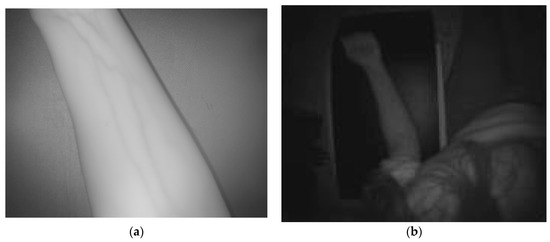

2.1. Multisensory System Description

2.2. Algorithm for Automatic Detection and Localization of Peripheral Subcutaneous Veins